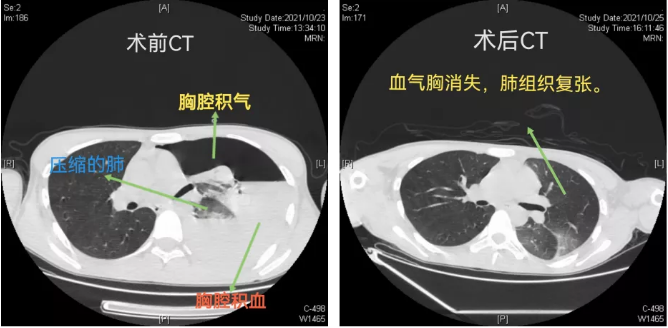

我院胸外科、心脏大血管外科主任、主任医师袁跃西介绍,当天患者由120救护车送到急诊科后,主治医师苏英杰迅速为患者完善胸部CT检查,结果发现其左侧大量液气胸,高度怀疑血气胸。苏英杰立即请胸外科、心脏大血管外科会诊,胸外科主任医师杨继承会诊发现患者面色苍白,心率达115次/分,血压低至80/50mmHg。行床旁胸腔穿刺抽出不凝鲜血。根据以上情况,杨继承当即判断患者出现了“自发性血气胸”,且已处于失血性休克状态,预计失血约达1500ml以上,病情危重。医院马上开通绿色通道将李峰由急诊送入手术室行胸腔镜下左侧开胸止血、肺大疱切除手术。

手术中,主刀医生杨继承发现患者左侧胸腔出血约有2000多毫升,胸顶有一撕裂小动脉出血,左上肺有多个肺大疱。立即用自体血回输装置进行胸腔出血回收,随后将出血小动脉用超声刀凝固止血,并将肺大疱切除,手术顺利完成,患者转危为安。